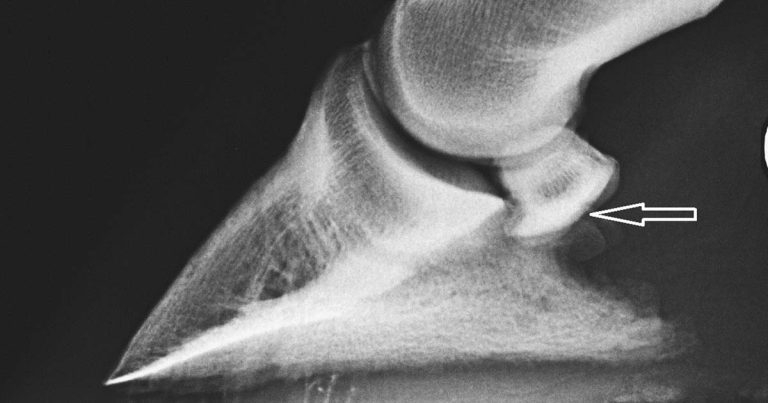

De Zani et al (2016) assessed the correlation of radiographic measurements of structures of the equine foot with lesions detected using MRI. Seventy-four feet of 52 horses with lameness localised to the foot underwent radiography and low-field magnetic resonance imaging. Objective measurements were obtained on radiographs.

Correlations existed between the thickness of the palmar compact bone of the navicular bone (Figure 4) and injuries of the deep digital flexor tendon (Figure 5), collateral sesamoidean ligament, navicular spongiosa and the proximal border of the navicular bone.

Long-toed horses had a high incidence of lesions involving the spongiosa and the proximal border of the navicular bone. Elongation of the navicular bone was associated with proximal and distal border injuries. A reduced palmar angle of the distal phalanx and increased angle between the middle and distal phalanges measured on the radiographs were seen in horses with abnormalities of the collateral ligaments of the distal interphalangeal joint and navicular bone spongiosa, respectively.

Recognition of such correlations might be useful to practitioners investigating foot pain without access to MRI. However, the relatively small number of horses and limitations of radiographic measurements in the study warrant interpretation of results with caution.